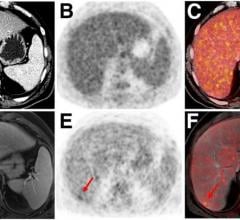

PET-MRI combines positron emission tomography (PET) and magnetic resonance imaging (MRI) into one imaging system. Positron emission tomography–magnetic resonance imaging (PET-MRI) is a hybrid imaging technology that incorporates magnetic resonance imaging soft tissue morphological imaging and positron emission tomography functional imaging.

December 10, 2021 — According to an article in ARRS’ American Journal of Roentgenology (AJR), MRI—with or without FDG ...